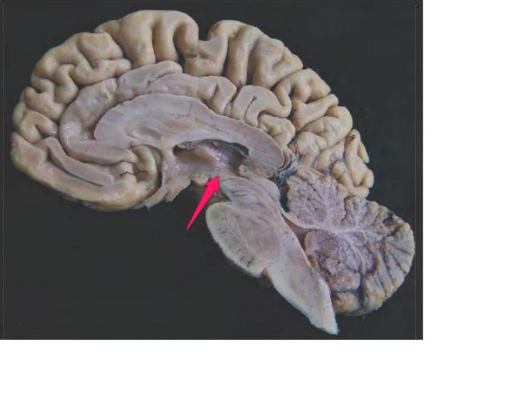

Aquaeductus mesencephali